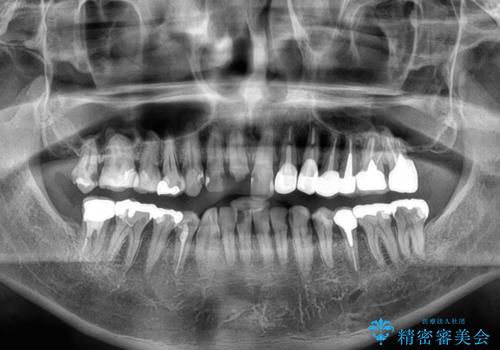

- すぐに欠けてしまう前歯や、むし歯で全顎的に処置された歯を気にして来院された患者様です。

元来むし歯が多く、さらに受け口傾向の咬み合わせを気にしていらっしゃいました。

当初はむし歯処置が必要な歯のみの治療予定でしたが、捻転や咬み合わせを可及的に改善したいとのことで、全顎的にオールセラミッククラウンにて補綴治療を行うこととしました。

反対咬合を補綴治療で改善すると、上唇へ歯が当たる感覚や、発音時の舌感覚が急激に大きく変化するため、違和感になれるまで時間を要することになります。

仮歯で過ごす期間を一定期間も受けることで徐々に変化になれていくようにし、オールセラミッククラウン装着時には違和感なく過ごすことができるようにしています。